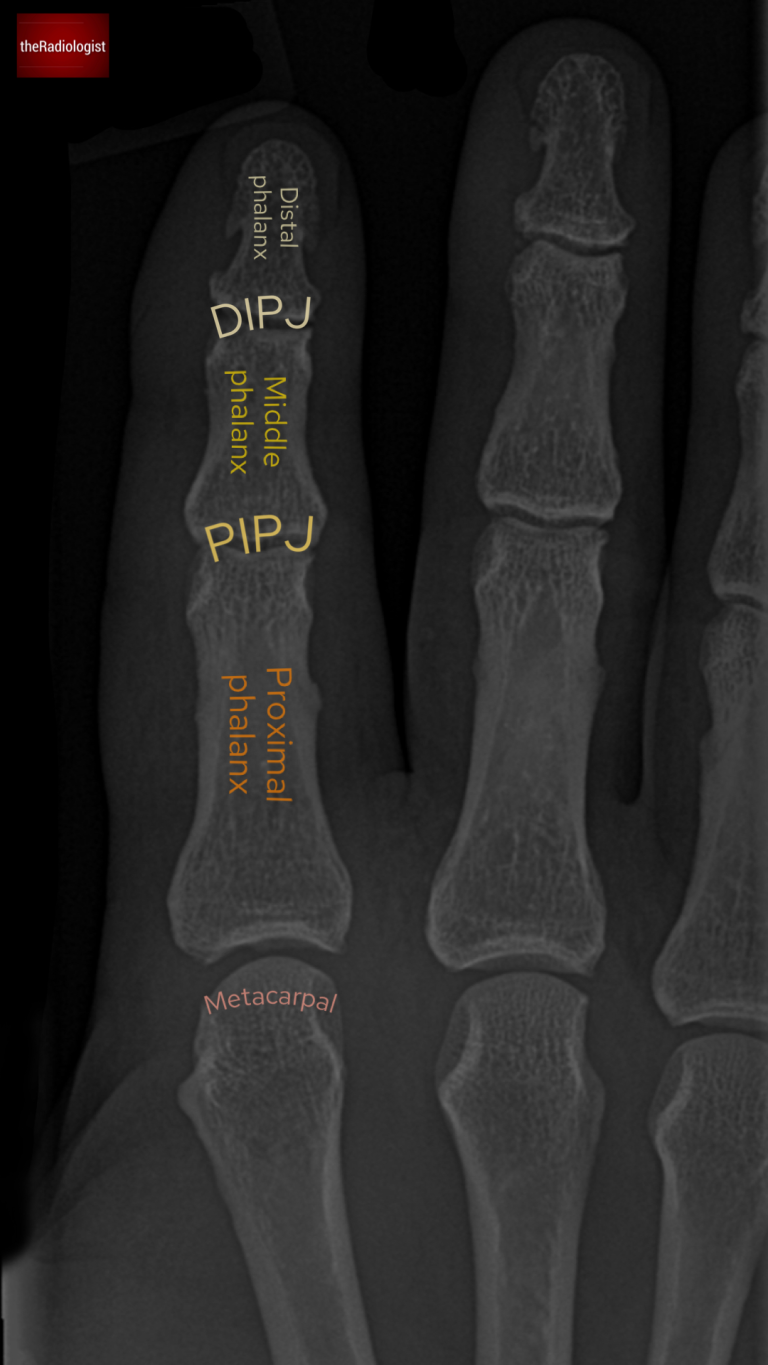

• Bones: Start by identifying the metacarpal, proximal phalanx, middle phalanx, and distal phalanx.

Annotated image of the PA view of the X-Ray showing the basic anatomy.